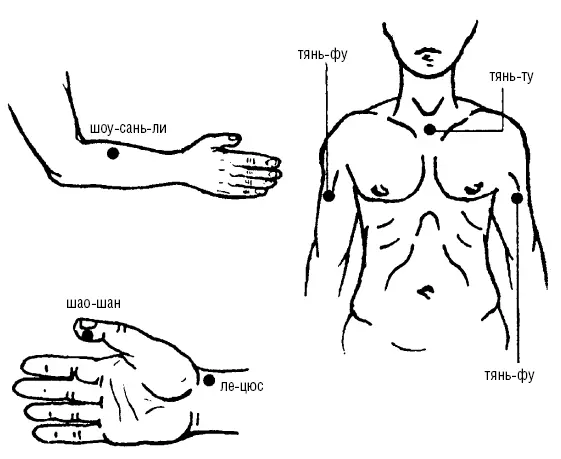

Рис. 113. При функциональных нарушениях органов дыхания

Методика точечного массажа седативная, успокаивающая, расслабляющая (рис. 113):

1. ШАО-ШАН (Р-11) находится у лучевого края концевой фаланги первого пальца, на уровне корня ногтя.

2. ЛЕ-ЦЮЕ (Р-7) находится на 1,5 цуня от лучевого края выше лучезапястной (медиальной) складки.

3. ШОУ-САНЬ-ЛИ (GI-10) находится на 2 цуня от точки ЦЮЙ-ЧИ, расположенной в конце локтевой складки при согнутой руке в локтевом суставе, на верхней трети наружной части предплечья.

4. ТЯНЬ-ФУ (Р-3) находится на передней поверхности плеча, на месте пересечения двуглавой и дельтовидной мышц плеча, при повороте головы в сторону поднятой вверх руки нос фиксирует искомую точку на руке.

5. ТЯНЬ-ТУ (1-22) находится в яремной вырезке грудины, в центре ее, на передней поверхности шеи.